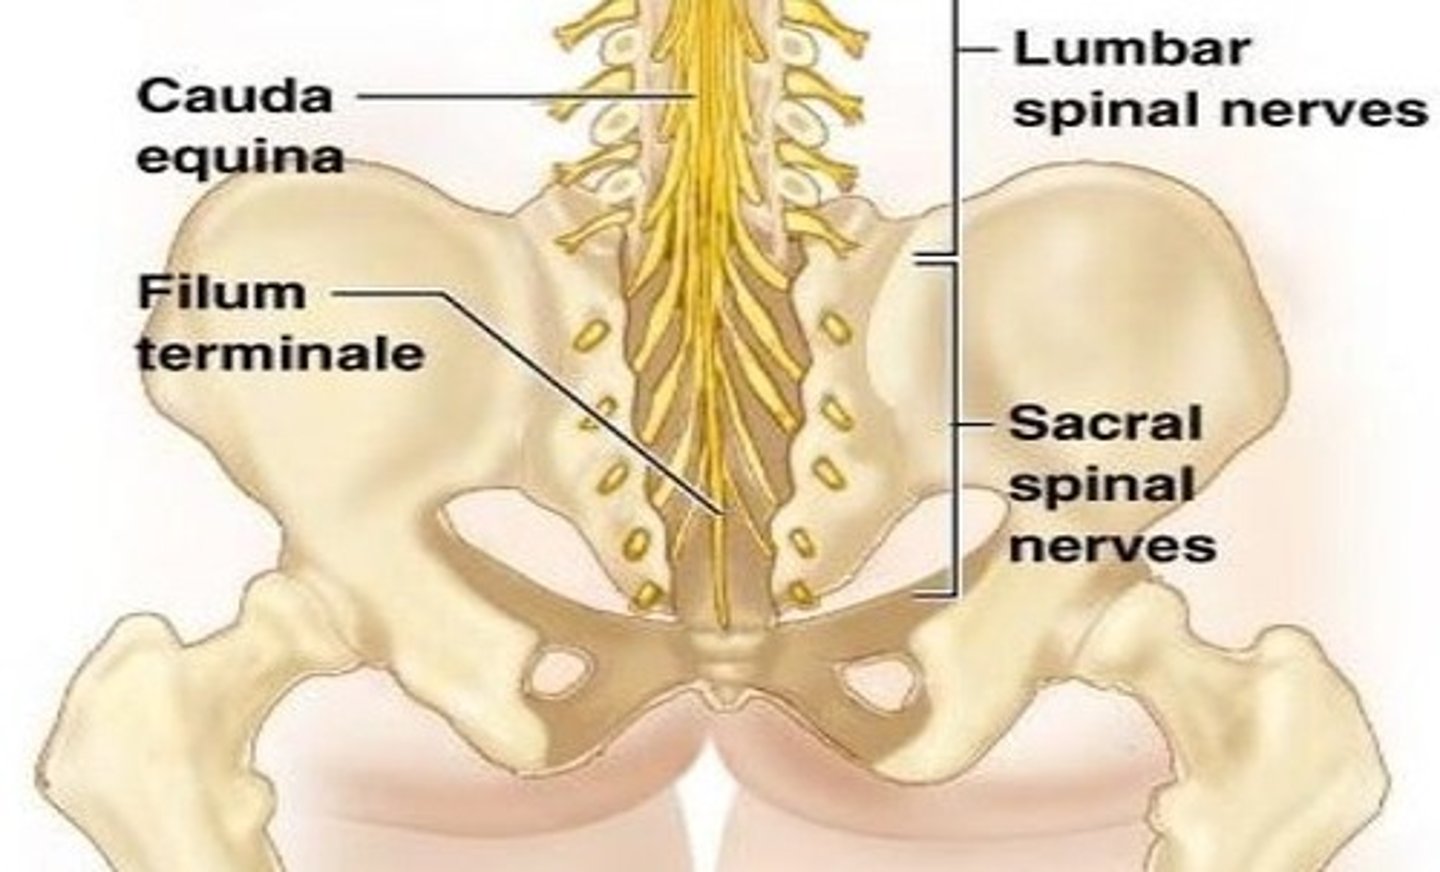

cauda equina

Nerve roots from spinal cord to lower intervertebral foramen to exit

L2 to S5 and filum terminale

filum terminale

anchors the spinal cord to the coccyx and sacrum